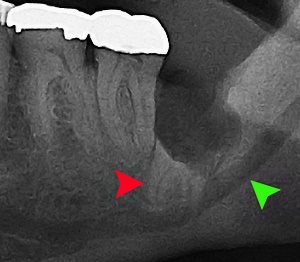

사랑니란?

우리가 사랑니라고 부르는 것은 큰 어금니 중 세 번째 위치에서 제일 마지막에 나오는 치아입니다. 사랑니가 나올 때에는 첫사랑을 하듯이 아프다고 하여 붙여진 이름이라고 하는데요. 다른 이름으로는 ‘지치’라고 합니다. 지치는 사리를 분별할 수 있는 지혜가 생긴다는 뜻입니다.

사랑니는 보통 큰 어금니와 비슷하게 생겼습니다. 사랑니의 형태나 크기는 매우 다양하다고 하는데요. 보통의 어금니 보다 깊이 나기 때문에 빼기 어렵거나 절개를 통해 힘들게 빼야 하는 경우가 많습니다. 원래 사랑니는 음식물을 갈아 내기 위한 용도라고 하는데요. 이것은 치아의 퇴화 현상이라고 생각하시는 분들도 많이 계십니다.